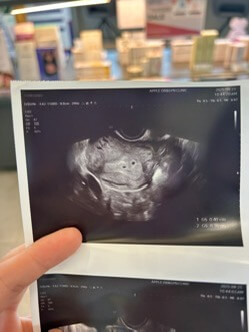

며칠 뒤 다시 초음파 검사를 했는데, 기적처럼 아기집이 보였어요!

처음엔 하나만 확인되었는데, 선생님이 좀 더 자세히 보시더니 위쪽에 또 하나가 있더라고요.

“아기집이 두 개네요.”

그 말을 듣는 순간, 안도와 기쁨이 한꺼번에 밀려왔어요.

그렇게 저는 감사하게도 이란성 쌍둥이 임신이라는 사실을 알게 되었어요.